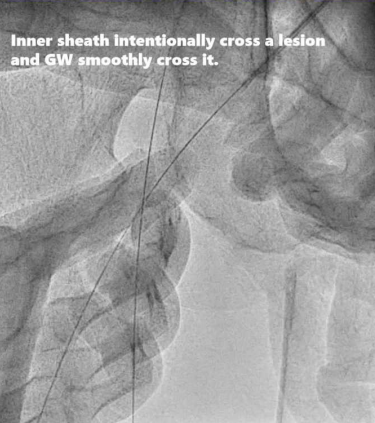

3、有意使扩张器穿过病变,并顺利通过GW导丝。

动脉长鞘怎么置入桡胜一筹丨原口拓也:经桡动脉入路在下肢动脉疾病腔内治疗中的优势——RADIANZ应用经验_https://www.jmylbn.com_新闻资讯_第24张